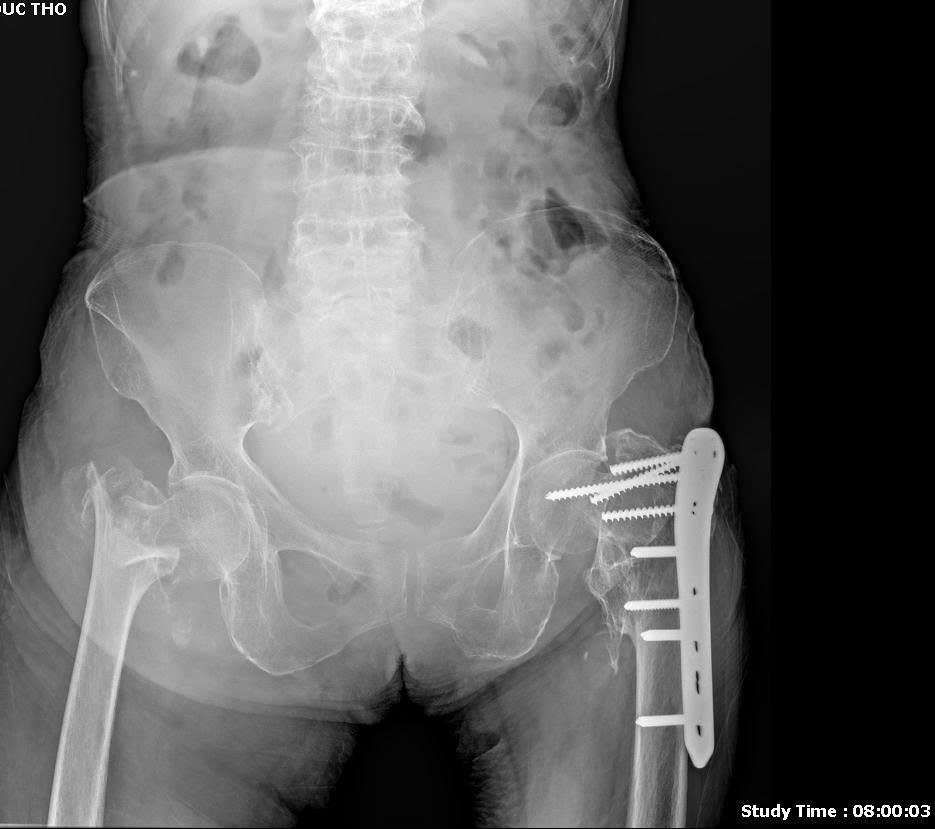

🍀Hình ảnh X-quang dưới đây mới chụp tại Hồng Hoàng cách đây ít ngày của một bệnh nhân lớn tuổi, cho thấy khớp háng bên trái là đã từng bị gãy phải phẫu thuật kết hợp xương bằng nẹp vít , còn khớp háng bên phải là mới bị gãy.

🍀Loãng xương là tình trạng rất phổ biến ở người cao tuổi, khiến xương trở nên giòn, yếu và dễ gãy. Trong đó, gãy cổ xương đùi là một trong những biến chứng nguy hiểm và thường gặp nhất. Chỉ cần một cú trượt chân nhẹ trong nhà, bước hụt cầu thang hoặc ngã khi đi lại cũng có thể dẫn đến gãy xương.